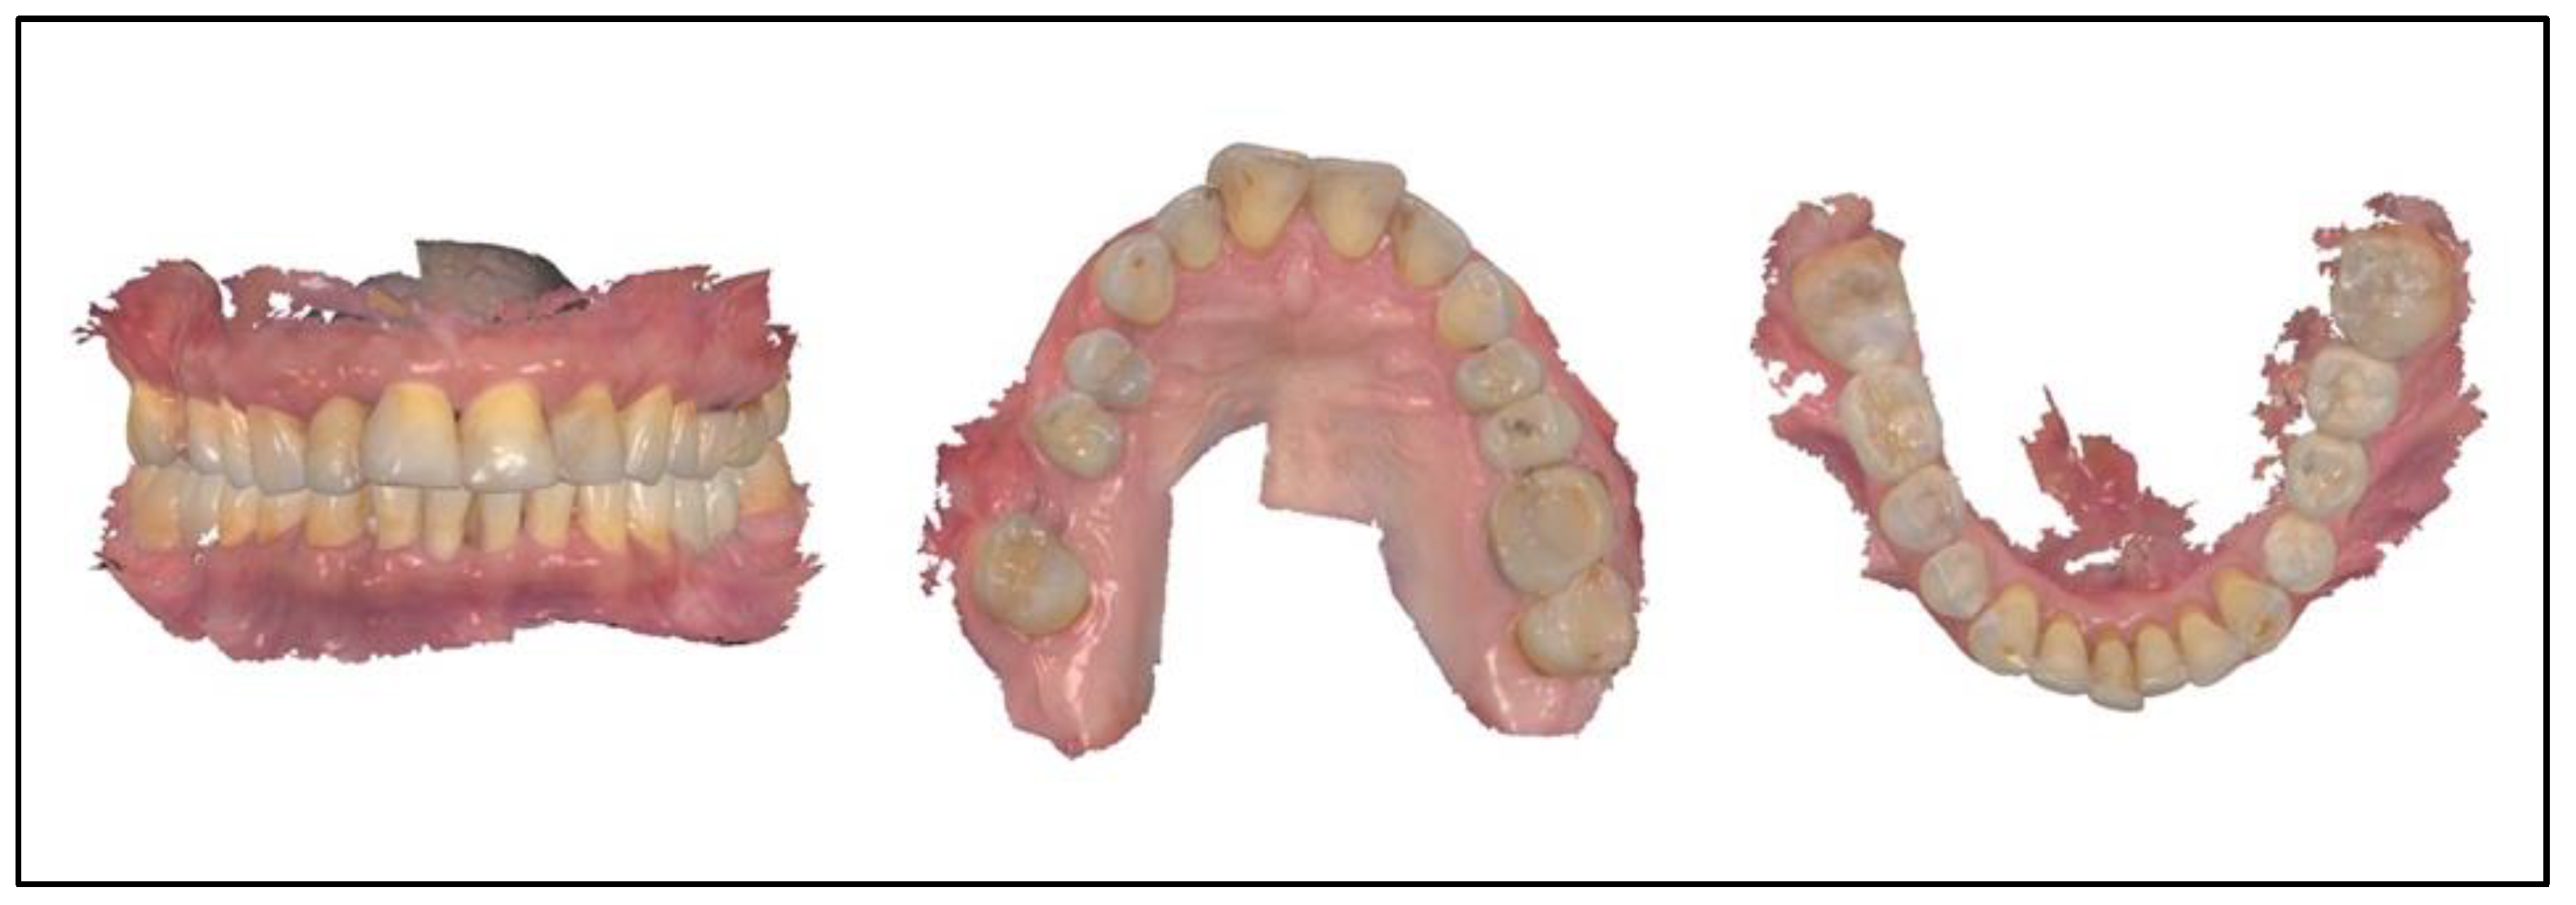

3.1. Case No. 1

3.2. Case No. 2